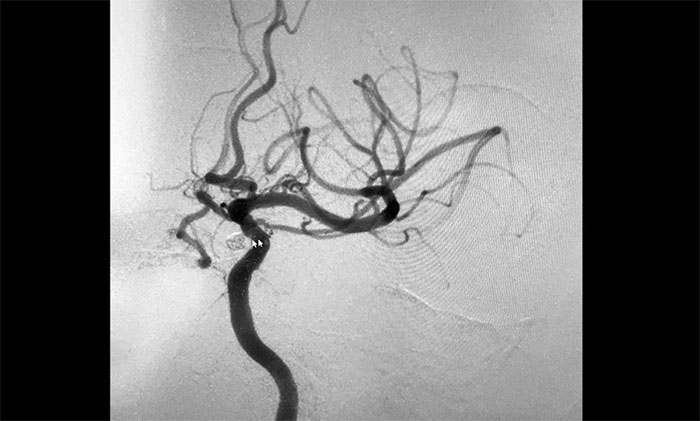

▲ 术后,成功栓塞动脉瘤并开通血管

术中,席刚明教授在王贵平博士及医护团队密切配合下,先对左颈内动脉C6段动脉瘤进行弹簧圈栓塞治疗,经Echelon-10微导管送入弹簧圈,成篮满意后暂不解脱;随后,微导丝引导球囊扩张导管头端置于左侧大脑中动脉M1段,球囊部分覆盖左颈内动脉C6狭窄段,进行球囊扩张,扩张后见左颈内动脉C6段狭窄明显改善,随后释放支架于左颈内动脉C7段至C4段,造影见左颈内动脉、左大脑中动脉、左大脑前动脉显影可。最后,继续栓塞动脉瘤,经Echelon-10微导管送入多枚弹簧圈,填塞满意后解脱,造影见动脉瘤基本不显影;复查造影,行3D造影见左颈内动脉、左大脑中动脉、左大脑前动脉显影可;行支架CT见支架成形满意,行XperCT未见颅内出血,手术圆满完成。